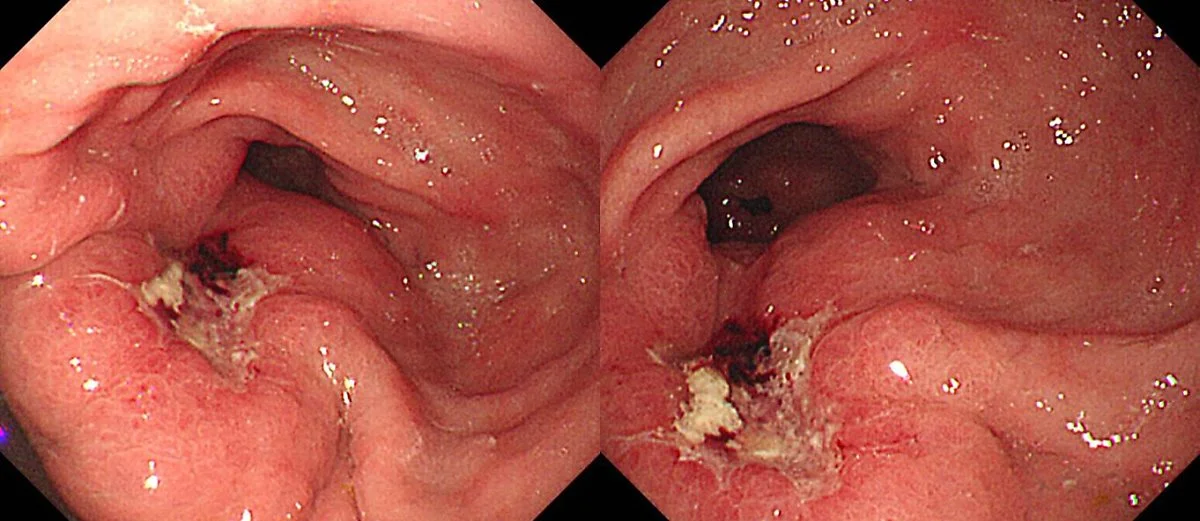

tube_01.jpg?type=w1200 EndoTODAY

지난해에는 구강 내 세균이 식도암을 유발한다는 연구결과도 나왔는데, '타네렐라 포르 시시가'라는 구강 내 세균이 식도암의 발생률을 21% 상승시킨다는 사실을 알아냈습니다. 식도암은 사망률이 높은 질병이기 때문에 이번 연구발표에 관심이 집중되고 있습니다.